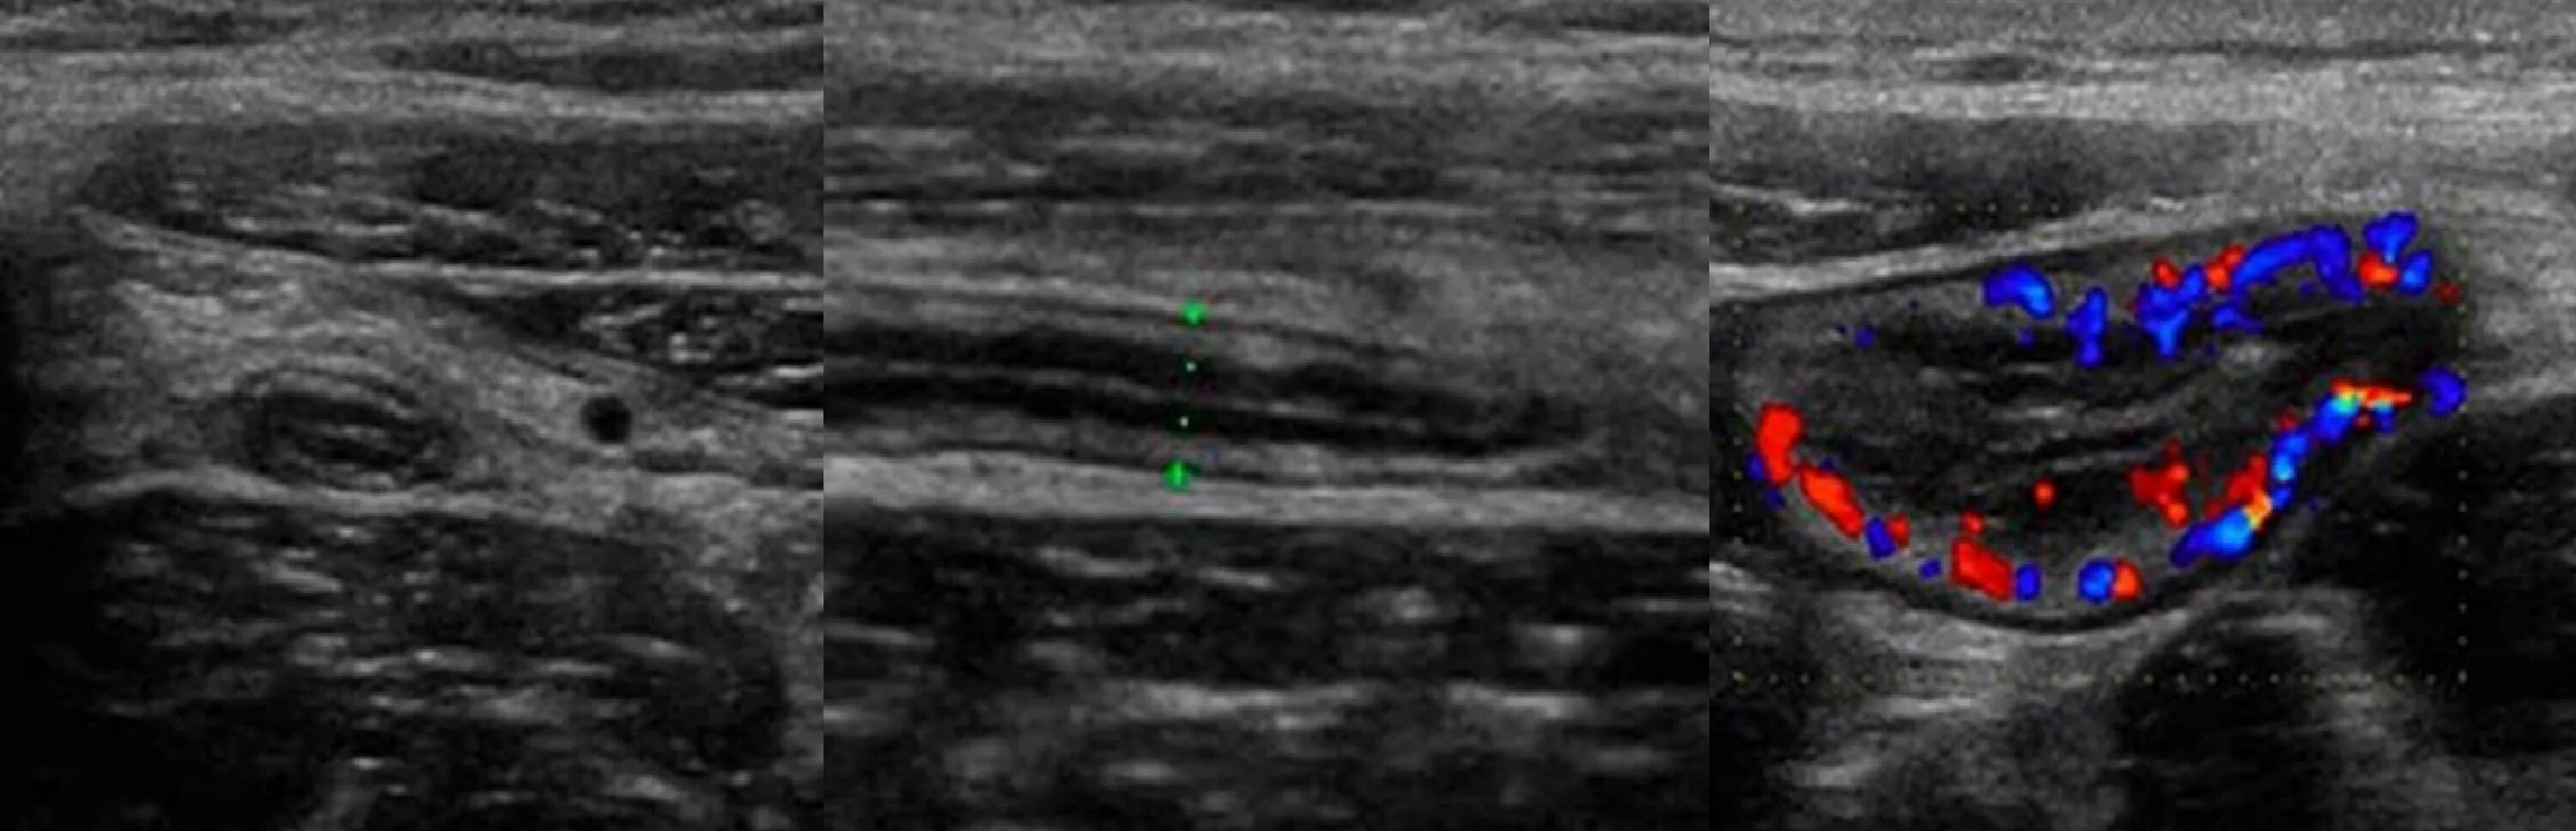

Аппендицит на узи можно ли